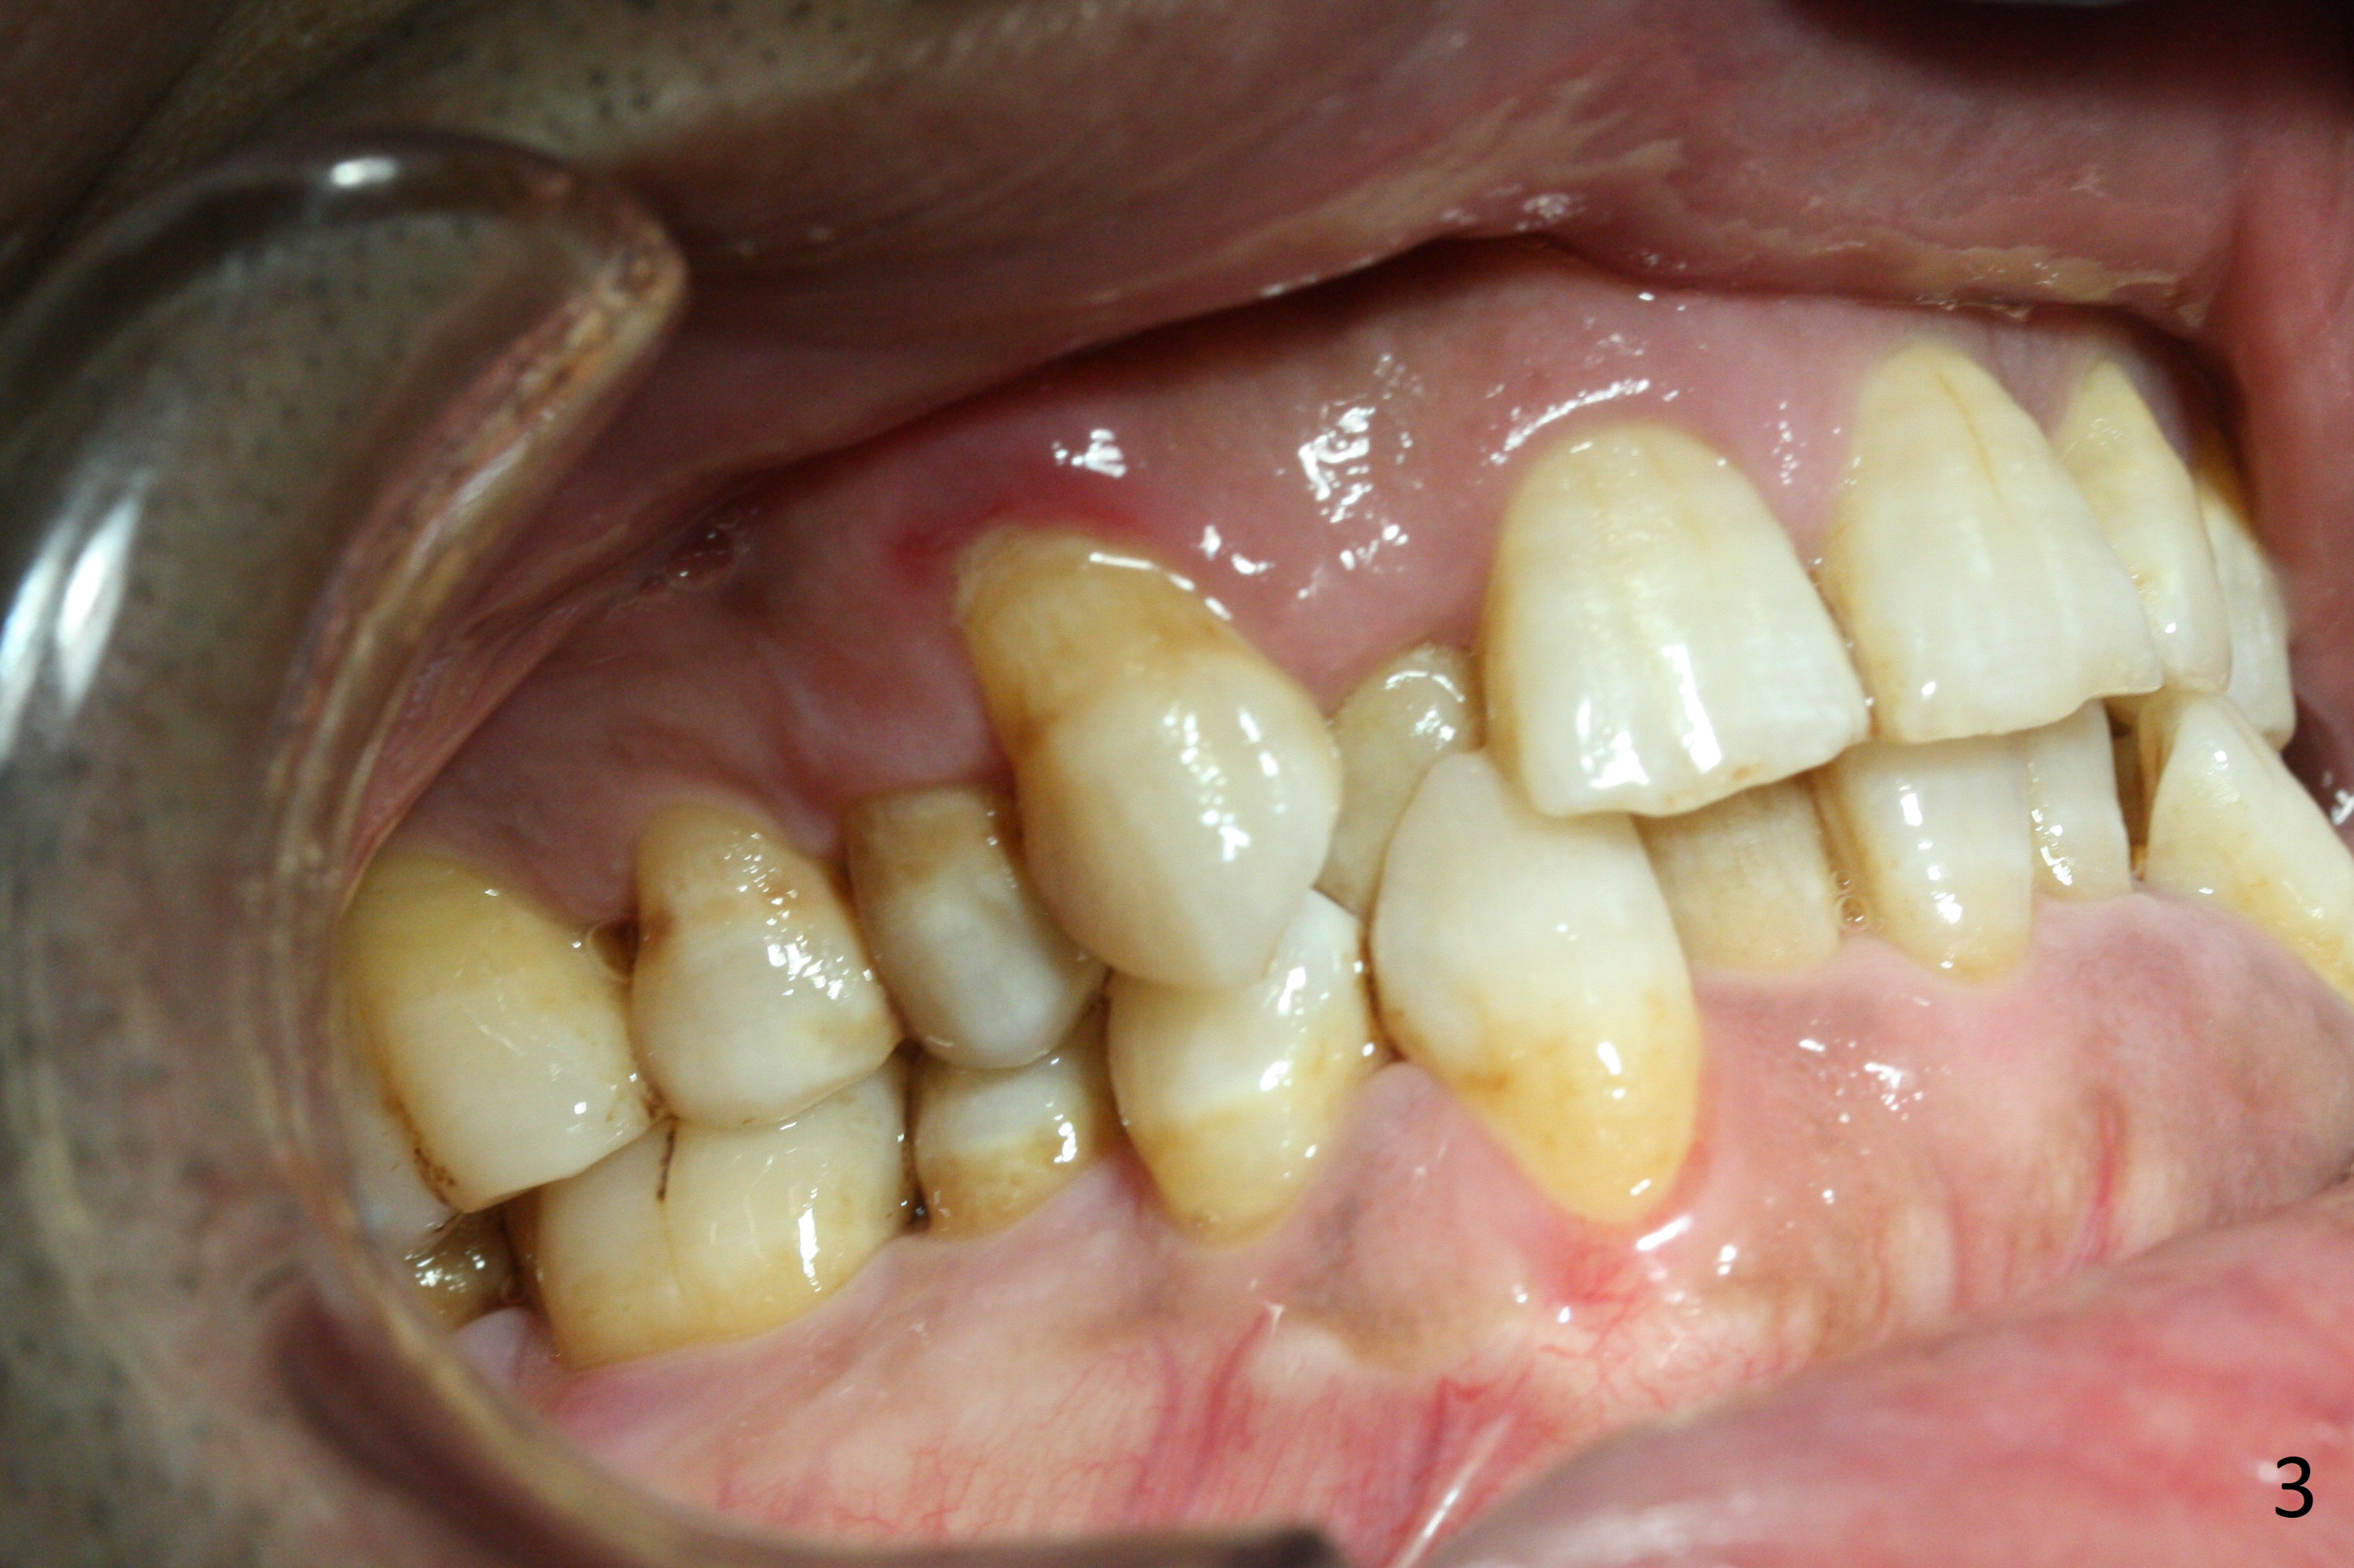

Enough Space For Crowding After Extraction? A 47-year-old man requests orthodontic treatment following SRP in other office (Fig.1-11). For severe crowding and midline shifting, extraction of four of the 1st bicuspids is imminent. Is it enough? To answer the question, model surgery is performed (Fig.12-16). 1st visit: periodontal maintenance, orthodontic consent (emphasizing oral hygiene) extract 4s and possibly L8s and separators. The beauty of this vist is that after local anesthesia and extraction including L8s, it is painless and easy to remove calculus from the proximal surfaces of the neighboring teeth. It is much easier to place separators after extraction. It is expected that there is no gingival erythema when the patient returns for bracketing. Take photos of UR3, similar to Fig.3. Molar banding is also anticipated to be easy with separator placement after extraction. Return to Ortho Cases Xin Wei, DDS, PhD, MS 1st edition 11/23/2017, last revision 04/28/2019